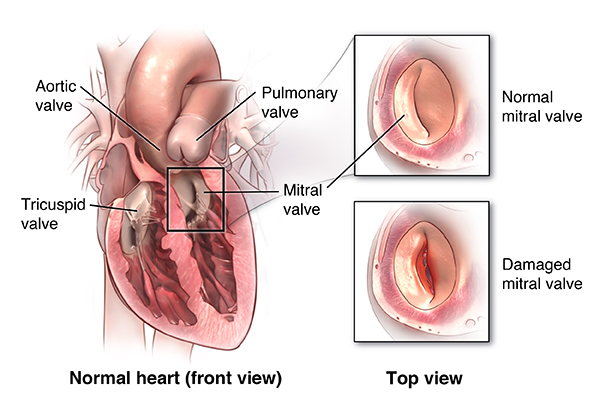

Value added benefits of the Mitral Valve Replacement:

Ø Doctor consultation charges

Ø Lab tests and diagnostic charges

Ø Room charges inside hospital during the procedure

Ø Surgeon Fee

Ø Cost of implant

Ø Nursing charges

Ø Hospital surgery suite charges

Ø Anesthesia charges

Ø Routine medicines and routine consumables (bandages, dressings etc.)

Ø Food and Beverages inside hospital stay for patient and one attendant.

Extra benefits:

ü Interpreter

ü Visa assistance

Ø Site tourism of the city

Ø Follow up with the doctor

Ø Airport pick up and drop

Ø Free online consultation with the doctor

Ø Priority appointments with the doctor

Ø Room upgrade from sharing to private